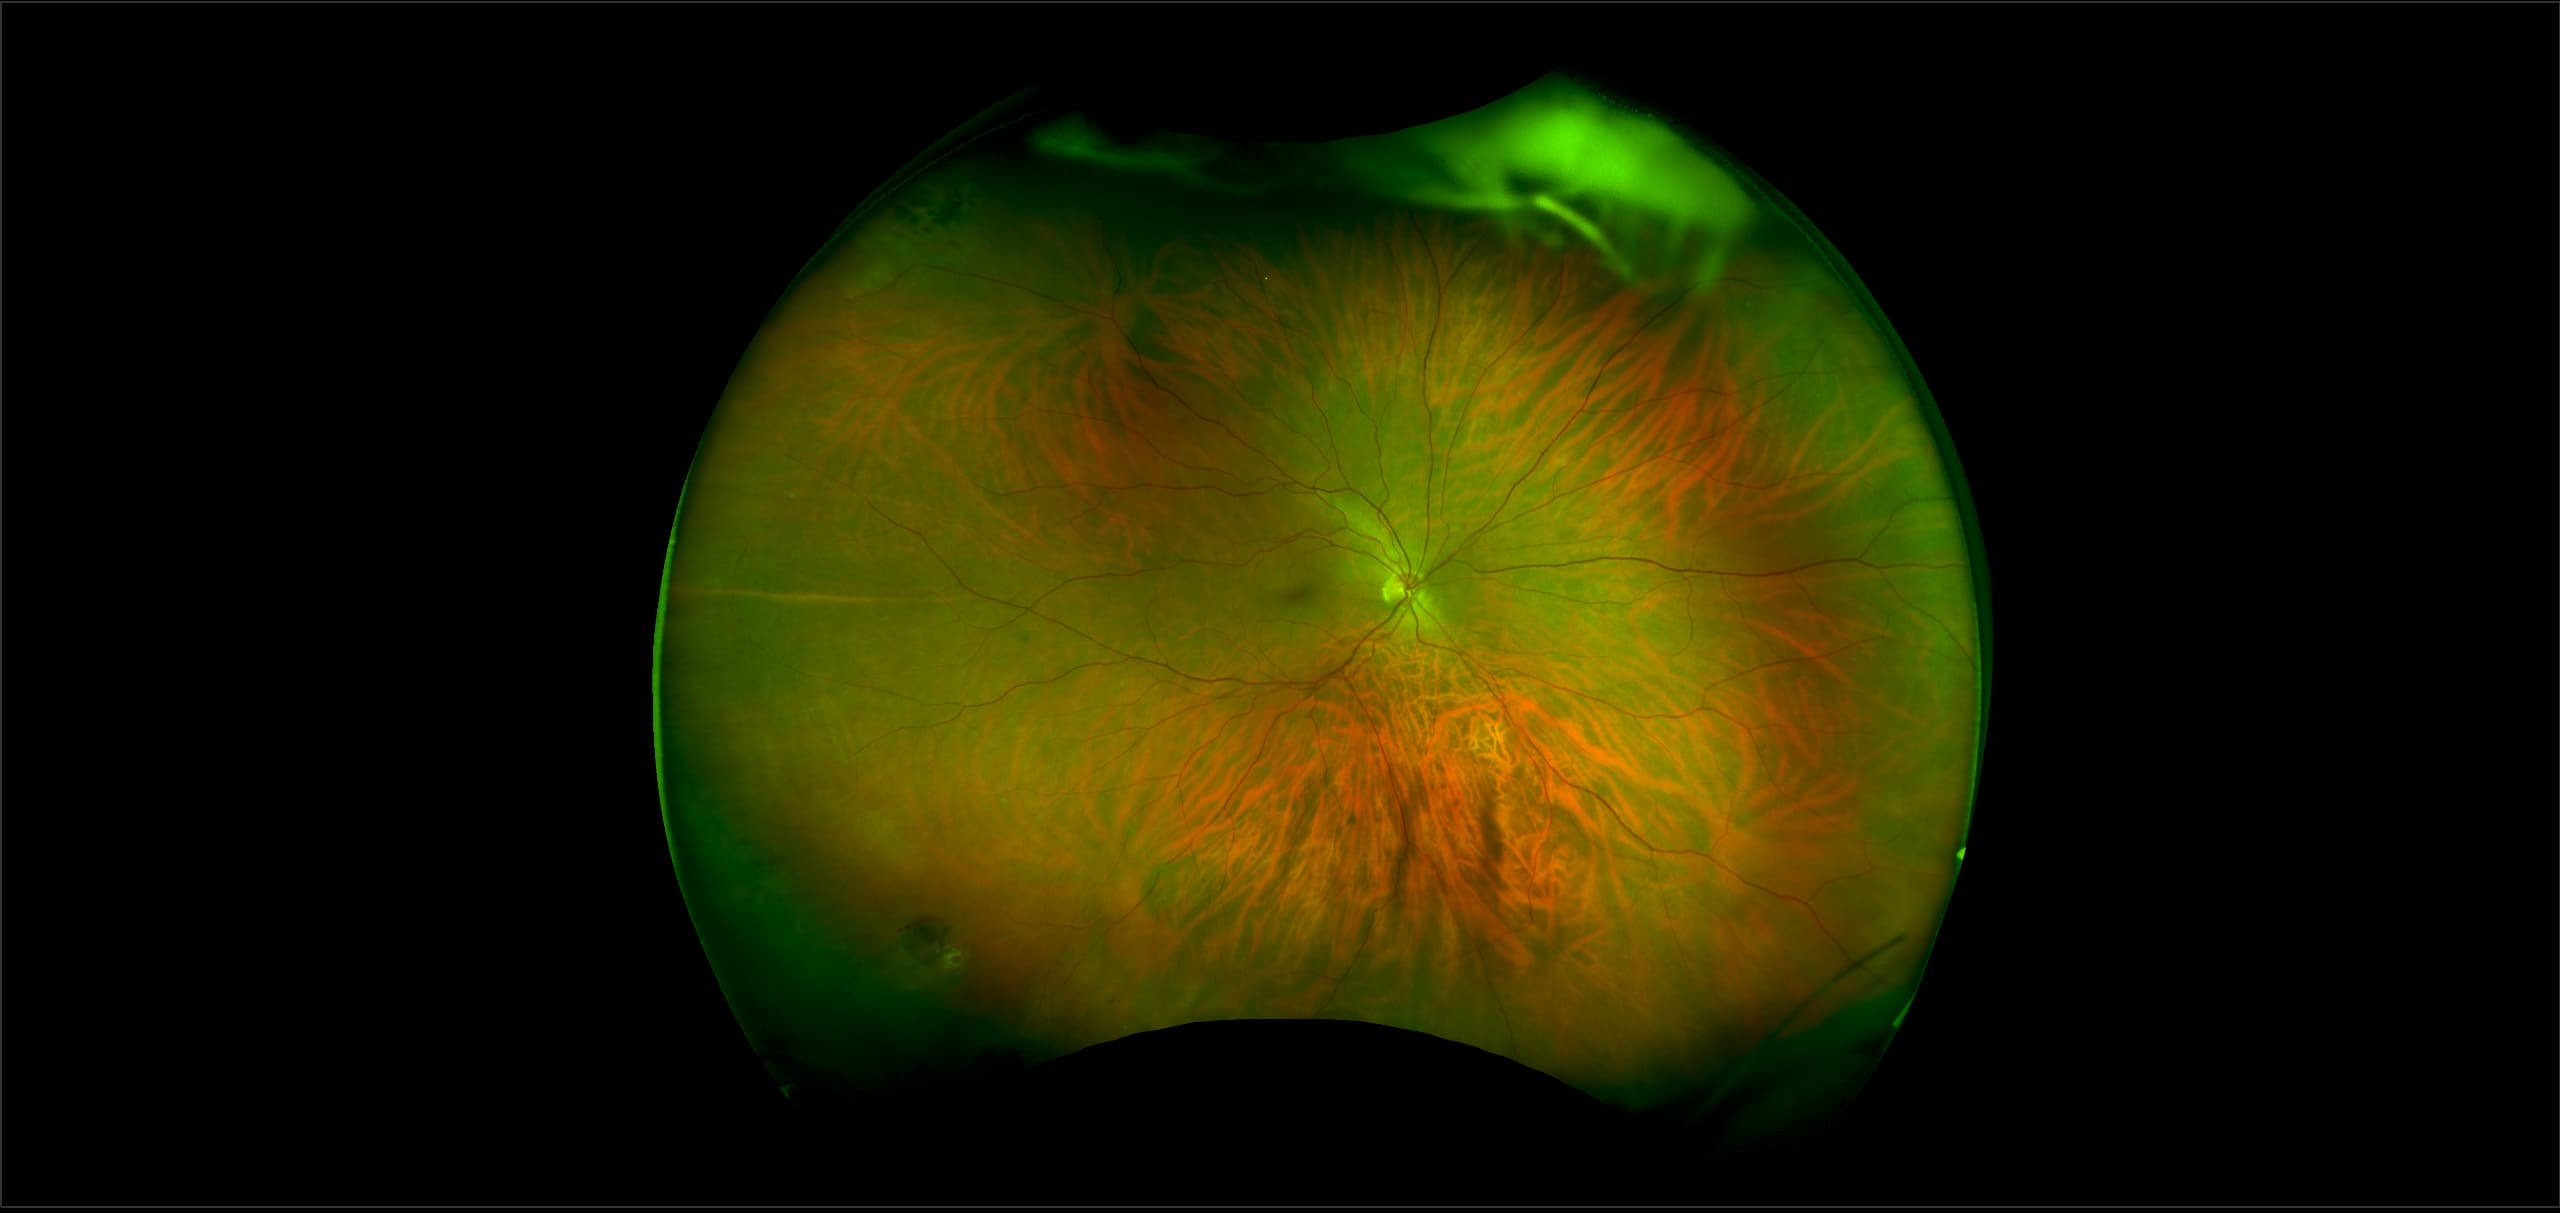

Monaco - Pigment Epithelial Detachment, RG, OCT